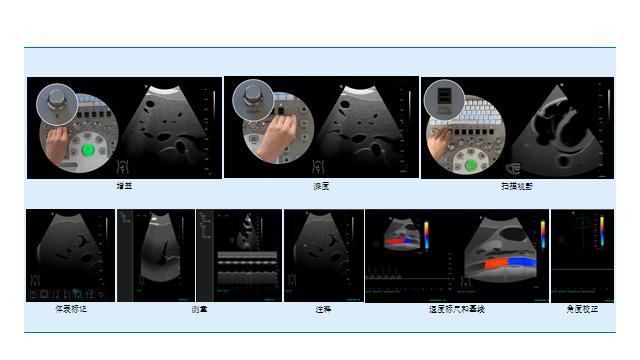

超声模拟实训系统 单机版(女)

超声模拟实训系统 单机版(女)

超声模拟实训系统 单机版(男)

超声模拟实训系统 单机版(男)

超声模拟实训系统 学生机

超声模拟实训系统 学生机

超声模拟实训系统 教师机

超声模拟实训系统 教师机